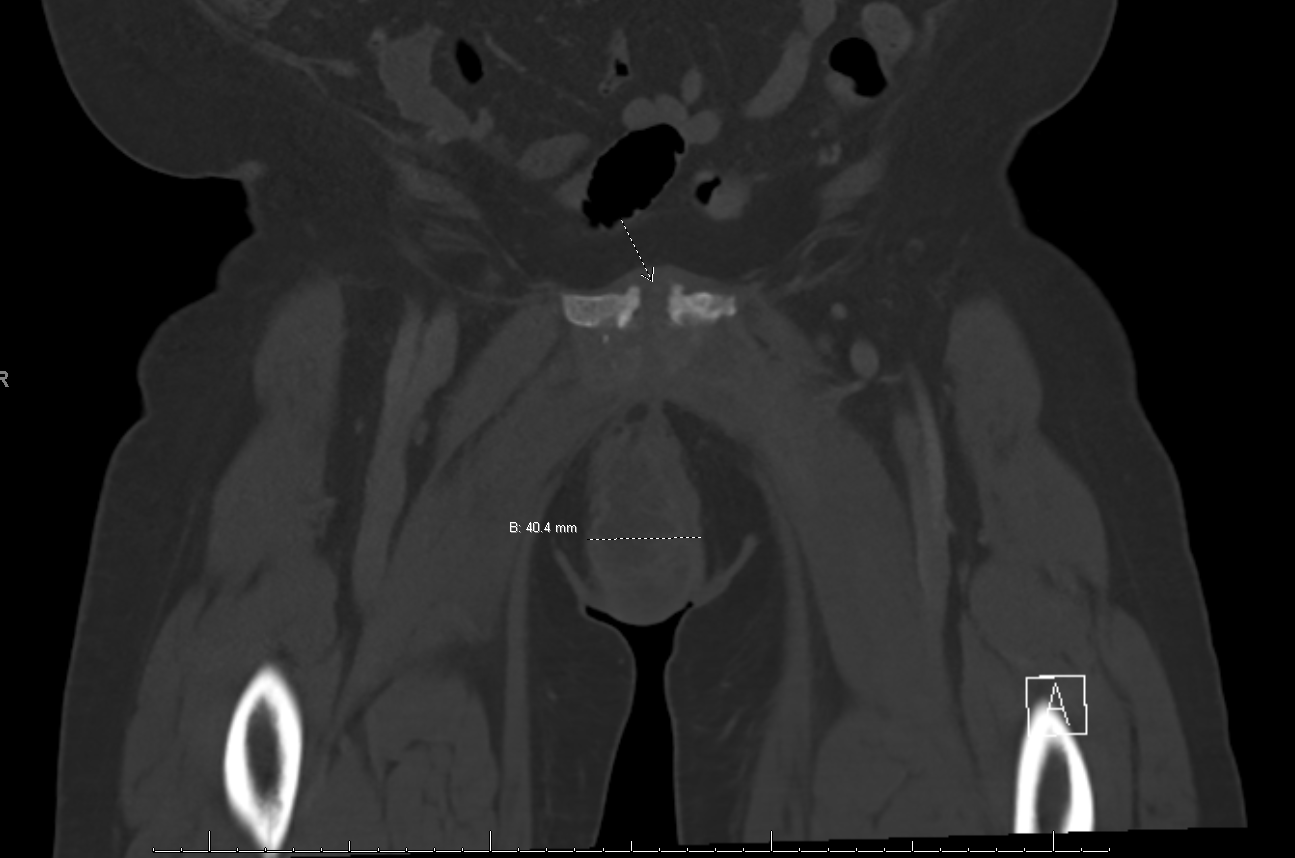

The patient presented to gynecology clinic for outpatient follow up three weeks after hospital discharge. She reported no further febrile episodes, however, her pelvic pain had returned. On repeat pelvic exam, a 6cm firm, well circumscribed, non-fluctuant, tender mass was palpated on right anterior vulva. Repeat CT pelvis was obtained and was remarkable for a 5.0 x 2.7 x 6.8-cm rim enhancing right labial abscess with concern for the superior aspect of the abscess extending to the pubic symphysis (Figure 1) (Figure 2).

Figure 1 Coronal view of CT pelvis showing rim enhancing right labial abscess with concern for the superior aspect of the abscess extending to the pubic symphysis.

Figure 2 Coronal view of CT pelvis showing rim enhancing right labial abscess with concern for the superior aspect of the abscess extending to the pubic symphysis.